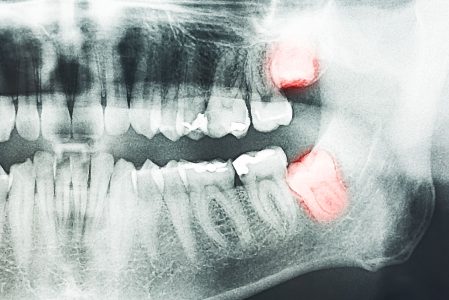

Signs You May Need Wisdom Teeth Removal

- Pain or discomfort in the back of the mouth

- Swelling or redness around the gums

- Crowding or shifting of nearby teeth

- Difficulty opening your mouth or chewing

- Initial Examination and Imaging: We perform a thorough oral exam and use advanced imaging, like Cone Beam 3D scans, to assess tooth position and plan the extraction.

At South Florida Institute of Oral Surgery, we use the latest dental technology to ensure safe and precise wisdom teeth removal. Our advanced tools, including digital X-rays and Cone Beam 3D imaging, allow our oral surgeons to evaluate tooth position, root structure, and surrounding bone with exceptional accuracy. This technology helps us minimize discomfort and reduce recovery time for patients undergoing wisdom teeth extractions in Coral Springs & Pompano Beach. By combining innovation with quality care, we provide a stress-free experience and promote optimal oral health for every patient.